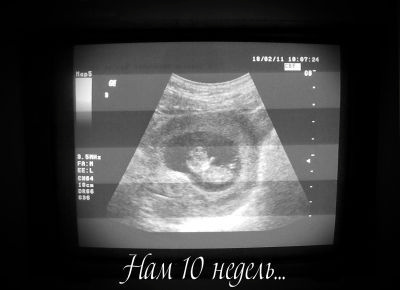

как увидела свою малышку то чуть не росплакалась… вот какая она бусинка )))

а когда 2 Узи делают????? ато так хочетьса вновь мою крошку увидеть)))![1 УЗИ)))]()

а когда 2 Узи делают????? ато так хочетьса вновь мою крошку увидеть)))

здорово!!! Второе делают примерно в 21 недельку! Легкой вам беременности!!!

здорово!!! Второе делают примерно в 21 недельку! Легкой вам беременности!!!